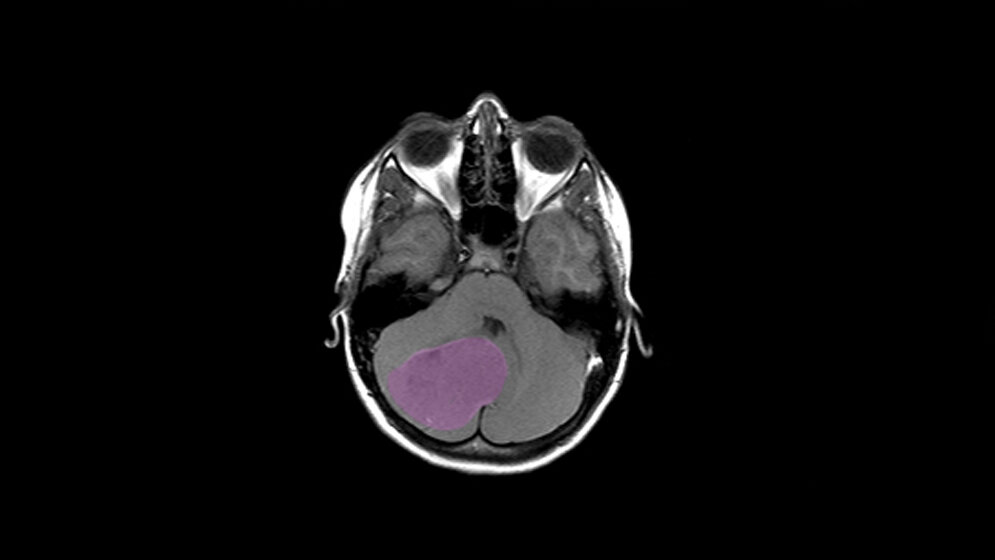

Medulloblastome sind bösartige Tumoren des Kleinhirns. Sie können in jedem Lebensalter vorkommen, meistens jedoch treten sie bei Kindern auf. Der Begriff Medulloblastom umfasst vier molekularbiologisch definierte Untergruppen, die mit sehr unterschiedlichen Krankheitsverläufen und Heilungschancen einhergehen. Kinder erkranken besonders häufig an Tumoren der Gruppen 3 und 4, die bislang wenig verstanden sind. Die Behandlung von Tumoren dieser Gruppe ist daher häufig schwierig. „Selbst wenn die Patienten gut auf die Behandlung ansprechen, werden sie oft zu einem hohen Preis geheilt, da sich die Therapie negativ auf das Gehirn, den IQ und die weitere Entwicklung der Kinder auswirken kann“, gibt Stefan Pfister, Wissenschaftler am Deutsches Krebsforschungszentrum, Oberarzt am Universitätsklinikum Heidelberg und Direktor am Hopp-Kindertumorzentrum am NCT Heidelberg (KiTZ), zu bedenken.